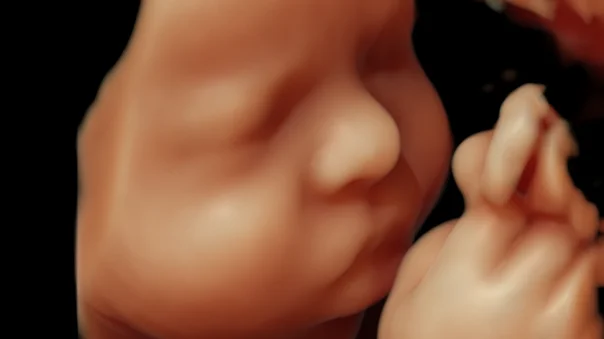

Madre, he ahí a tu hijo: así es una Ecografía 7D , con la que ya se pueden ver detalles del cerebro y el corazón

Esta tecnología cumple seis décadas con nosotros. Ahora, los nuevos equipos permiten ven a los bebes con una nitidez extraordinaria, como si hubiera una cámara dentro del vientre materno. Incluso, hasta usan Inteligencia Artificial.